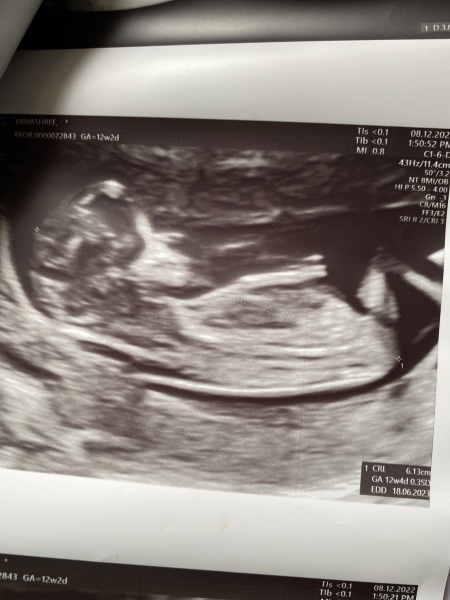

Vanashree03 · 05/01/2023 05:46

What is the gender of the baby based on skull and nub theory

Skull theory

Vanashree03 · 05/01/2023 05:53

Hii I m 116 weeks pregnant I seek the help of you all to know the gender of the baby based on skull and nub theory

thank you